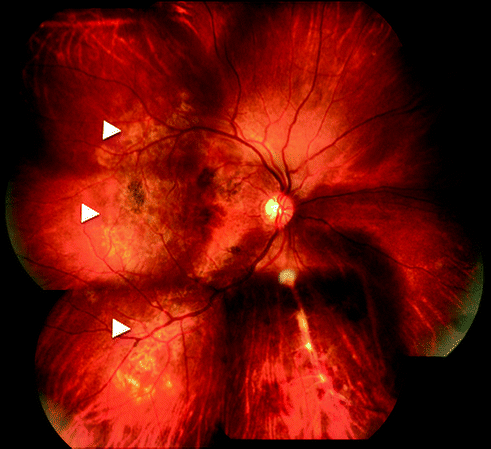

Fig. 15.2

Fundus photograph of right eye showing multifocal serpiginoid choroiditis (arrowheads) associated with retinal vasculitis and hemorrhages along inferonasal quadrant

The most common manifestations of tubercular posterior uveitis in ophthalmic practice are retinal vasculitis and multifocal serpiginoid choroiditis. Different manifestations of posterior uveitis may co-exist in the same or opposite eye (Fig. 15.2). The posterior uveitis can be accompanied by generalized intraocular inflammation (panuveitis), anterior, and intermediate uveitis.